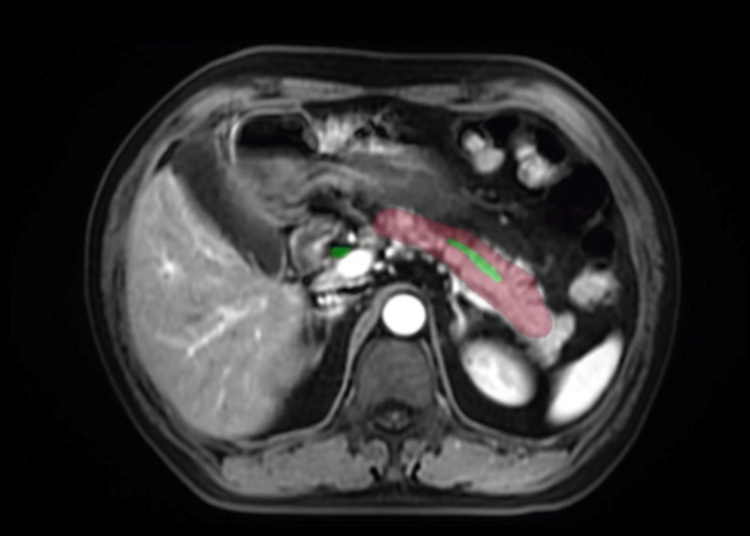

在宣传影片中,影为医疗工程师通过自主研发的计算机软件Medraw系统,将患者的二维平片转化为三维视图:

我们利用MRI增强序列显示胰腺及病灶边界,可以清晰看到胰腺的钩突、胰头、胰颈、胰体和胰尾。

利用MRCP序列勾画胰胆管,显示肝内胆管、肝总管、胆囊、胆囊管、胆总管主胰管